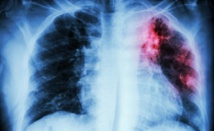

TB gets to be transferrable when the microbes that cause the malady goes through the air and is breathed in by someone else. The most well-known organs influenced by the microbes are the lungs, yet it can likewise hit the kidneys, bones and mind. TB is normally harder to treat than different irresistible infections, and it takes six to nine months to finish a whole treatment regimen. XDR-TB is far more terrible than standard sorts of TB, with just 30-50 percent of cases cured, contrasted with the last, which quite often yield a positive reaction to the treatment.